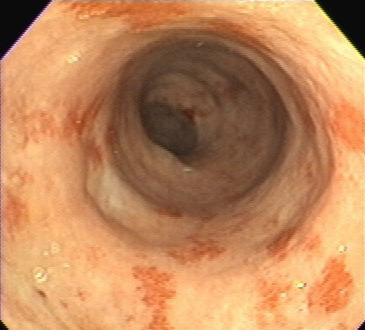

Клиническая картина язвенного колита - НЯК © Ulcerative colitis

Язвенного колита больше нет! Полное излечение неспецифического язвенного колита